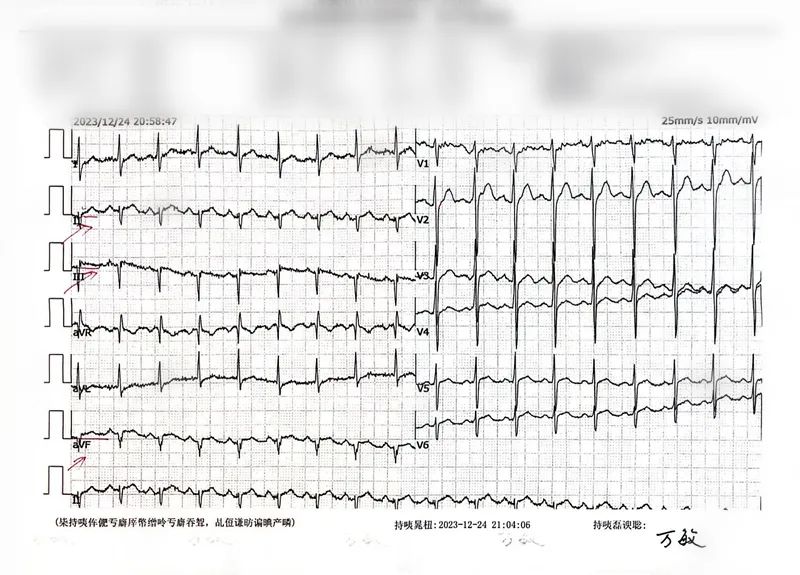

患者林先生(化名)吃酒席后出现胸闷不适症状,未予重视,两天后胸闷难忍,背部疼痛,遂至我院急诊就诊。血压171/110mmHg,心电图提示下壁有心梗可能,肌钙蛋白:0.86ng/ml,初步诊断为:急性心肌梗死,考虑到患者既往有长期高血压、高血糖、高血脂病史,情况刻不容缓。

造影结果,倒吸凉气!

完善各项检查后,胸痛中心王力主任立即启动胸痛救治绿色通道,征得家属同意,对患者紧急实施冠状动脉造影术+支架植入。

手术顺利,患者心血管开通,自感胸痛、胸闷明显缓解。